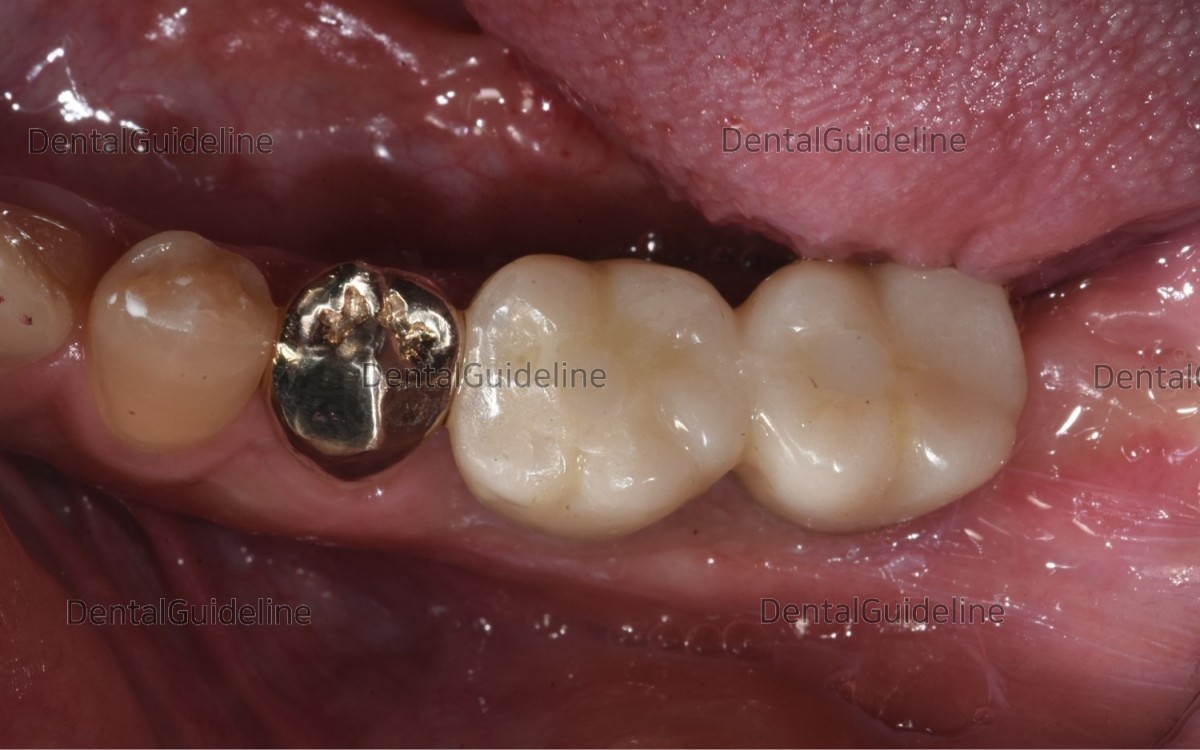

After taking an impression, customized abutments and crowns were fabricated by the dental lab.

Abutments were connected to the fixture.

The pick-up impression was taken in the condition of crown seating in the mouth. The lab was asked for ceramic to be added on the occlusal surface due to insufficient occlusal contact with opposing dentition.

Final cementation and hole filling with composite resin.